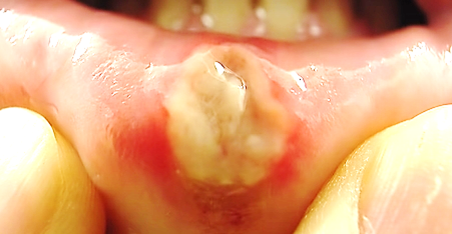

◈ 구내염 치료법

순서대로 해보세요.

1. 노출된 속살을 소독해줍니다. (헥사메딘)

아침, 저녁 두 번 가글 해서 소독해줍니다.

2. 통증억제

상처부위를 화학적으로 지져 줍니다. (알보칠)

면봉으로 상처부위에만 살짝 찍어 바릅니다.

짧고 굵은 통증이 동반됩니다.

얇은 껍질이 상처를 덮어서 통증을 완화해줍니다.

3. 염증치료

오라메디는 강력한 소염작용 성분인 스테로이드가 들어 있어 염증을 치료해줍니다.

이 외에도 상처 부위에 붙이는 아프타치도 있습니다.

1,2,3번 순서대로 식사 때마다 반복해서 해줍니다.